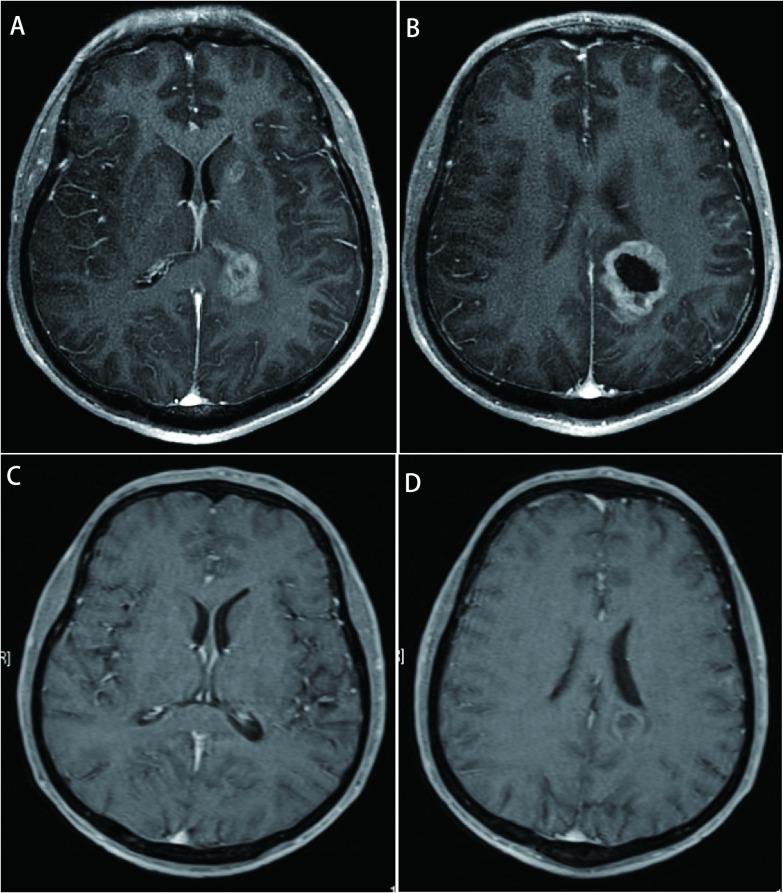

left lower lobe adenocarcinoma T1bN2M1a stage IV. Fluorescence in situ hybridization (FISH) indicated the translocation of ALK (2p23) chromosome. After 2 cycles of docetaxel+cisplatin (DP) regimens chemotherapy, disease progression occurred, so we used 6 cycles of pemetrexed+carboplatin to apply combination chemotherapy, 4 cycles of pemetrexed monotherapy were used after that. The efficacy evaluation: PR. On April 9, 2016, the patient was treated with crizotinib. In August 2019, multiple intracranial metastases were found and whole brain radiotherapy was given. Since September 4, 2019, oral administration of nsatinib has been carried out. As of March 1, 2021, the patients were followed up well.

左肺下叶腺癌T1bN2M1a Ⅳ期。荧光原位杂交(FISH)检测提示ALK(2p23)染色体易位。多西他赛+顺铂(DP)方案化疗2周期后疾病进展,换用培美曲塞+卡铂联合化疗6周期,之后采用培美曲塞单药化疗4周期。疗效评估:PR。2016年4月9日患者接受克唑替尼治疗。2019年8月发现多发颅内转移,给予全脑放疗。自2019年9月4日起口服恩扎替尼。截至2021年3月1日,患者随访情况良好。